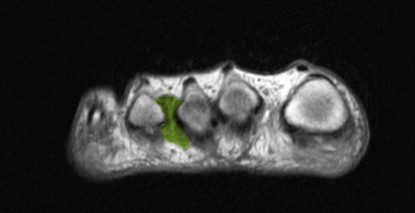

Morton Neurome ab 0,3 cm können von einem erfahrenen Radiologen im MRT-Bild ziemlich sicher nachgewiesen werden. Eine gute MRT-Untersuchung mit Größenbestimmung ist eine wichtige Voraussetzung für die operative Behandlungsentscheidung: Bis zur Größe von maximal 0,6 bis 0,8 cm können wir das Morton Neurom ohne Nervenamputation (Neurektomie) behandeln.

Darstellung des Morton Neuroms durch bildgebende Verfahren

Nachdem das Morton Neurom durch die klinische Untersuchung und eine genaue Betrachtung des Krankheitsverlaufes und der Symptome gesichert wurde, kann eine MRT es darstellen. Durch die MRT (Magnetresonanztomografie) kann der Arzt andere Ursachen für die Mittelfußschmerzen weitgehend ausschließen. Ein Röntgenbild eignet sich nicht, ein Morton Neurom zu zeigen.

Die MRT-Untersuchung ist vor allem wichtig, um eine Größenbestimmung der Nervenschwellung vorzunehmen. Von der Größe des Morton Neuroms hängt auch seine Behandlung ab. Je kleiner das Morton Neurom, desto eher lässt es sich konservativ behandeln.

Doch auch in der MRT wird das Morton Neurom häufig übersehen. Der Radiologe benötigt spezielle Einstellungen des Kernspintomografen, um bei so feinen Strukturen wie dem Mittelfußnerven eine Schwellung nachweisen zu können.